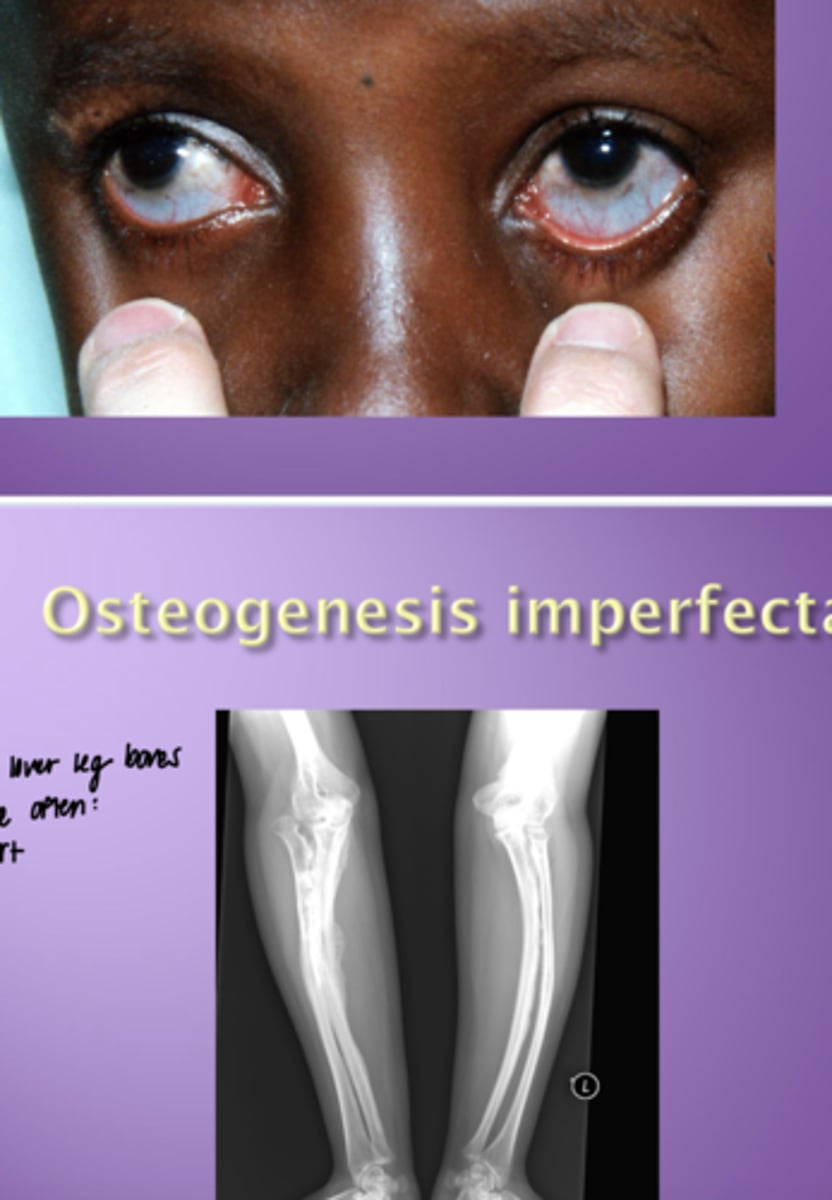

Osteogenesis imperfecta

- characteristics

- Blue sclera

- Bowed leg bones (pts often short)

Osteogenesis imperfecta is associated with what dental disorder?

Dentinogensis imperfecta

Characteristics of OI

- discolored and weak teeth

- wear of enamel

- pupil dilation

- blue slcera